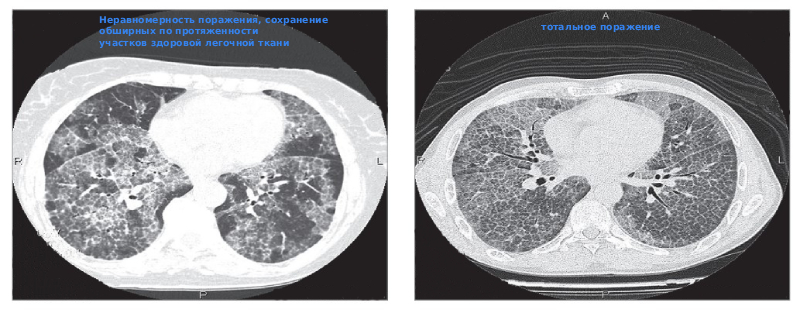

- КТ: даёт более чёткую картину. Выявляет участки уплотнения с чёткими границами.